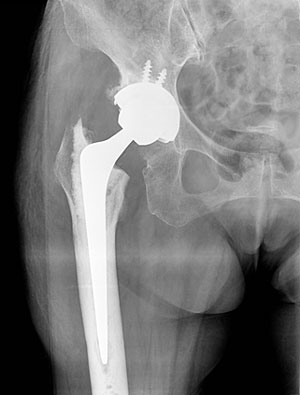

全人工股関節置換術

手術後、約2、3日後より、立位訓練等のリハビリを実施していき、深部静脈血栓症予防や股関節周囲筋群の強化、脱臼防止を指導していきます。

手術後